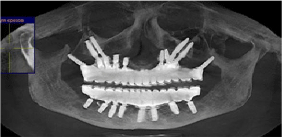

A 46 years old patient, presented to our clinic with a diagnosis of generalized periodontitis of the lower jaw, with edentulous atrophic maxilla. A comprehensive clinical and radiographic evaluation revealed advanced alveolar bone resorption rendering the prognosis of all lower teeth unfavorable. After the preliminary clinicalradiation examination, a treatment plan was defined that included the removal of all the teeth of the mandible and the installation of 8 dental implants in lower jaw, the installation of 1 dental implants in the tuber regions of the upper jawbone on both sides, the installation of 2 dental implants in zygomatic bone from both sides and installation 4 dental implants in the area of 13,14,23,24 distant teeth. 4 months after implant placement prosthetic restoration was fabricated and adjusted. The patient has been followed up for 5 years. So far, no further problem has occurred and the restoration has remained functional (Figures1-8).

Figure 2: CT scan after 1 month surgery.